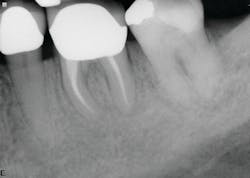

The first case involves a 49-year-old female. Tooth no. 31 had a deep periodontal probing on the straight buccal. The patient was warned that the tooth might be fractured, but she still decided on treatment (figure 1).

Calcium hydroxide paste medication was placed in the canals on three visits, each two weeks apart. Treatment included a total of six weeks of calcium hydroxide therapy.